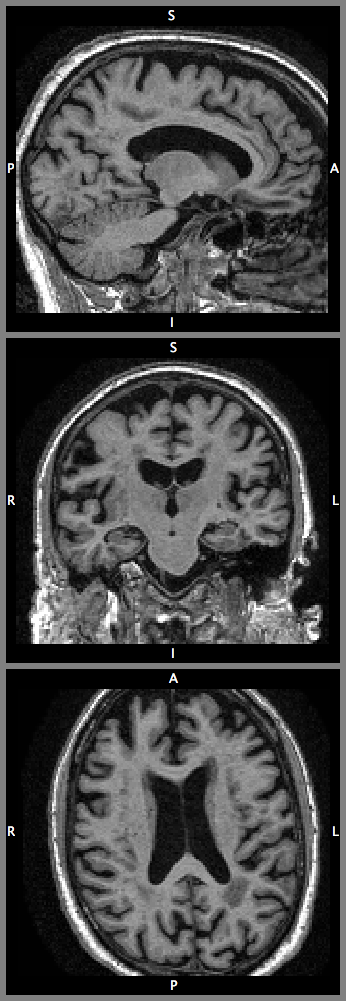

4.0.1 Data.

To demonstrate the feasibility of learning complex 3D image representations from large-scale data, the proposed network is learning a highly granular segmentation of T1-weighted MR images of healthy controls from the ADNI dataset. The average number of voxels of each volume is about . The average voxel size is approximately . All volumes are bias-corrected and reoriented to a standard Right-Anterior-Superior orientation. The bronze standard parcellation of brain structures and non-brain outer tissues are obtained using the GIF framework [1]. Fig. 5(left) shows the label distribution of the dataset. We randomly choose 443, 50, and 50 volumes for training, test, and validation respectively.